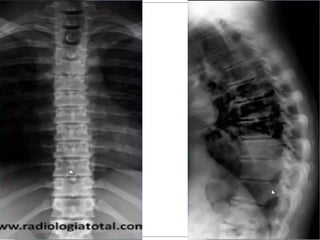

Cifose

Lordose

Hipercifose Torácica

Hiperlordose Lombar

Escoliose

Definição: Desvio do eixo da coluna vertebral no plano frontal, acompanhado de rotação dos corpos vertebrais.

Solicitação: Raios-x panorâmico da coluna vertebral em posição ortostática

Cifose/Lordose

Quando exageradas são anormais e chamadas de HIPERLORDOSE e HIPERCIFOSE. Quando diminuídas também são anormais e chamadas de REDUÇÕES NAS CURVATURAS FISIOLÓGICAS, RETIFICAÇÕES OU INVERSÕES NAS CURVATURAS FISIOLÓGICAS.

Etiologia: má postura, raquitismo , tuberculose,etc...